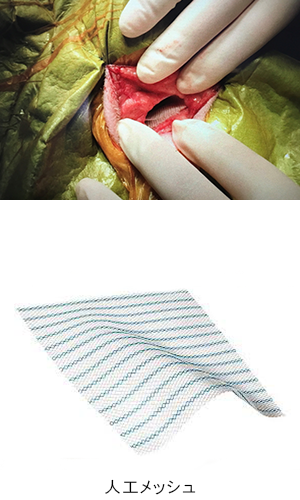

| 会陰ヘルニアは、高齢の未去勢の雄犬に多い疾患です。会陰(お尻の周囲)部の筋肉間がゆるんで腹部臓器がお腹の中から皮下にとび出して(ヘルニア)しまう病気です。 この症例は、腸、膀胱、前立腺が皮下へとび出しており、もう少しで排尿ができなくなり致命的な状況になるところでした。 本症例は人工メッシュを用いて会陰ヘルニア整復手術を行いました。術後は排便排尿もスムーズにでき、経過も良好です。なお、会陰ヘルニアは再発率が高い疾患であり、術後も日常ケアや経過観察が必要となります。 |